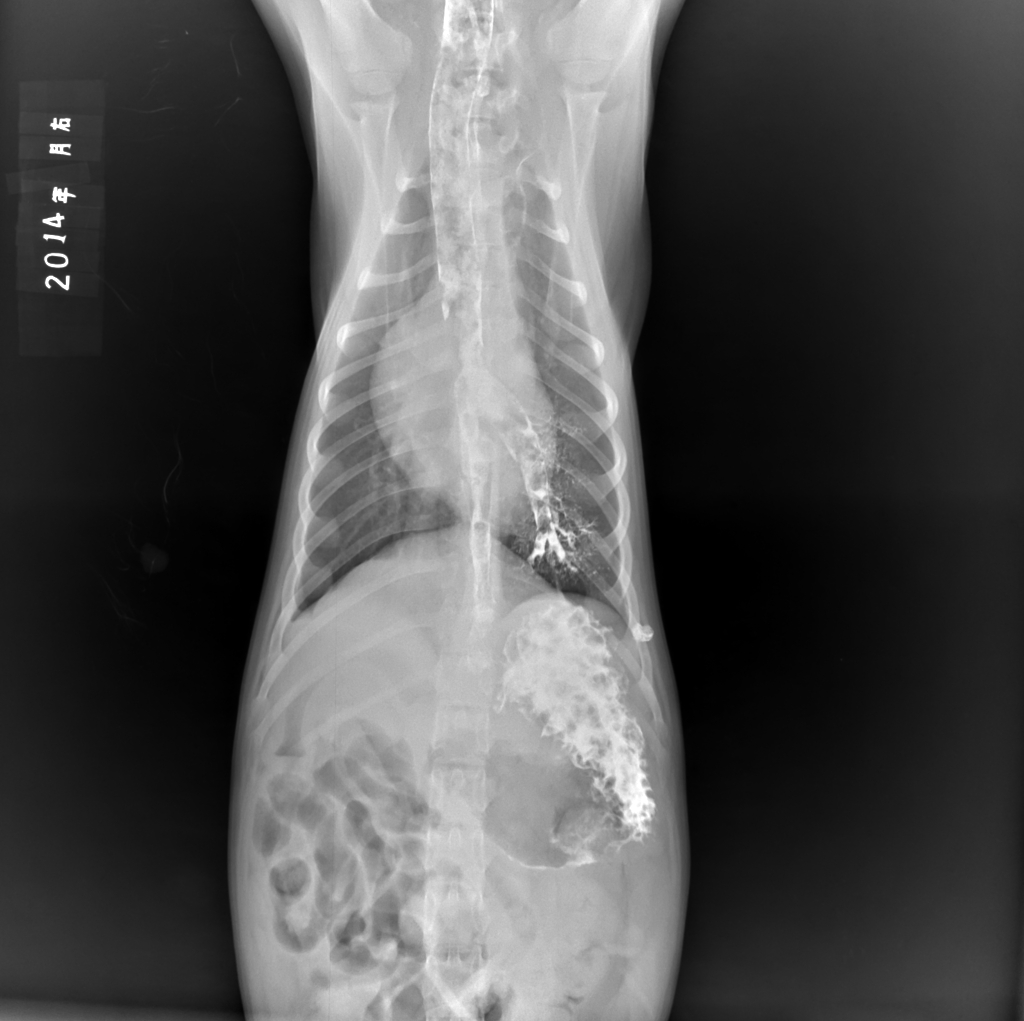

食道造影犬吞咽困难造影剂吞咽进入气管和肺正位